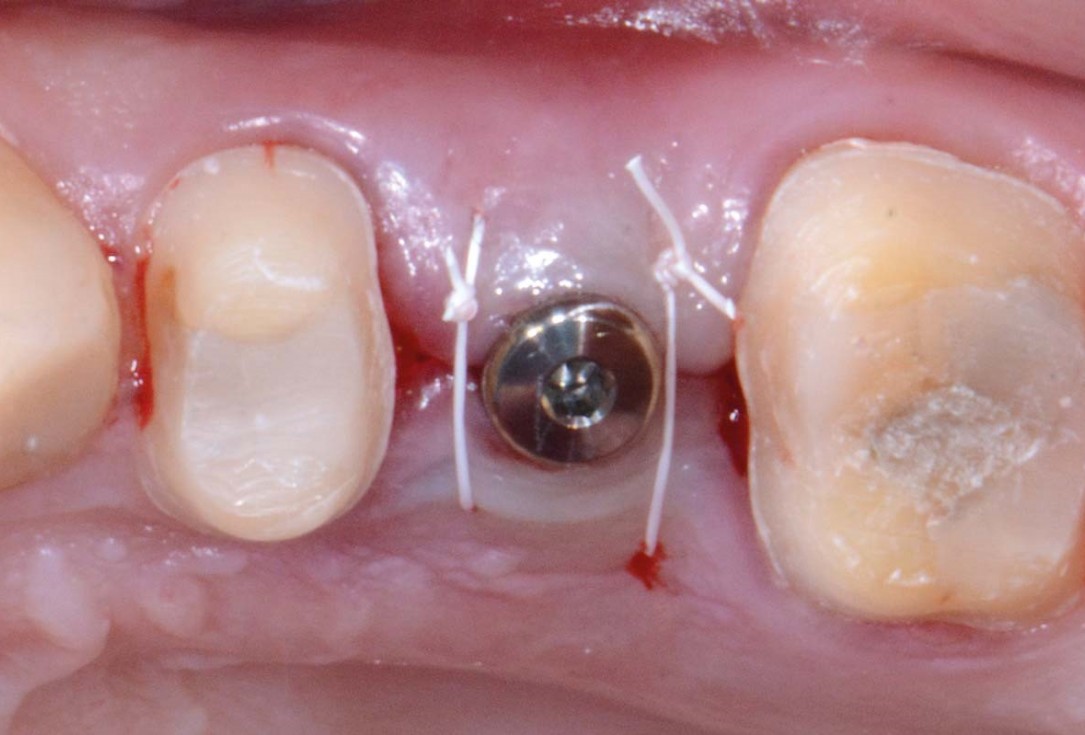

13/16 - Flap closure after implant placementFull bone regeneration in extraction socket augmented with maxgraft® and Jason® membrane – Dr. C. Landsberg